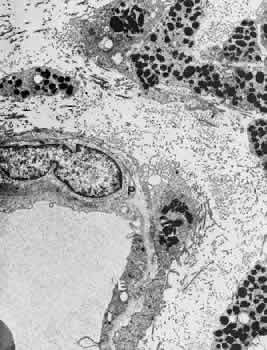

distribution. Invest Ophthalmol Vis Sci 27:1659, 1986 9. Hogan MJ, Feeney L: Ultrastructure of the retinal vessels, part 1. The larger vessels. J Ultrastruct Res 9:10, 1963 10. Yamada E, Shikano S: Electron microscopy. In Atlas of Ophthalmology. Tokyo, Igaku

Shoin, 1972 11. Justice J, Lehmann RP: Cilioretinal arteries. Arch Ophthalmol 94:1355, 1976 12. Das A, Frank RN, Zhang NL et al: Ultrastructural localization of extracellular matrix components in human